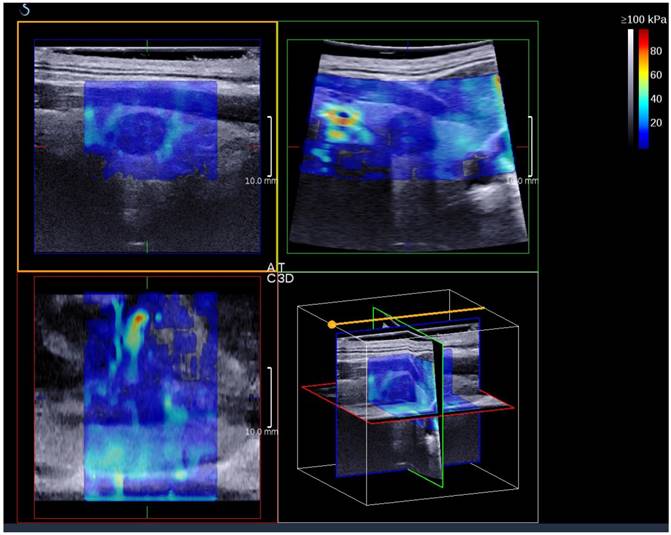

3D SWE examinations were performed by an SLV 16-5 probe of AixPlorer US system (SuperSonic Imagine, Aix-en-Provence, France). The volume imaging was automatically performed by using a slow-tilt movement of the sectorial mechanical probe, which was placed with very light pressure to show the longest diameter of nodule in transverse section and kept stably until the end of automatic scanning. Volume data were reconstructed and displayed as multi-slice images (sagittal, transverse, and coronal images) (Fig. 2). For each section, 8 slice images could be caught by fixing the top slice and the bottom one, which should touch the margin of nodule in order to include the most elastic information as possible (Fig. 3). In each slice, quantitative elasticity values were measured using Q-box as in 2D SWE. 3D-Emean was the mean value of Emean of all slices in each section, and 3D-Emax was the largest value of Emax of all slices.

Figure 2

A thyroid papillary carcinoma on the sagittal/transverse/coronal section by 3D SWE

J Cancer Image